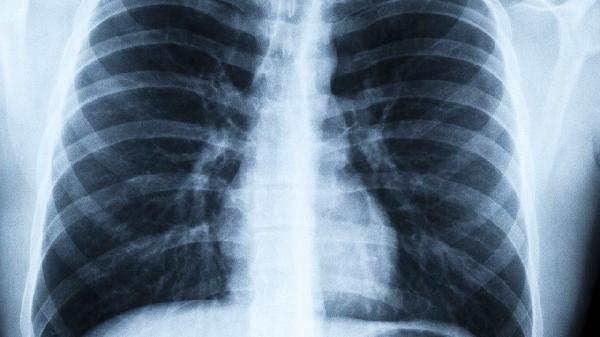

女性成为肺癌新宠,多因这2点!建议女性都看看

提到肺癌,很多人第一反应是“老烟枪”的专属病,但近年来,肺癌的“目标人群”似乎悄悄发生了变化——女性患肺癌的比例正在逐年上升。这可不是危言耸听,而是实实在在的数据。为什么肺癌开始“盯上”女性?背后隐藏的2大原因,值得每一位女性关注。